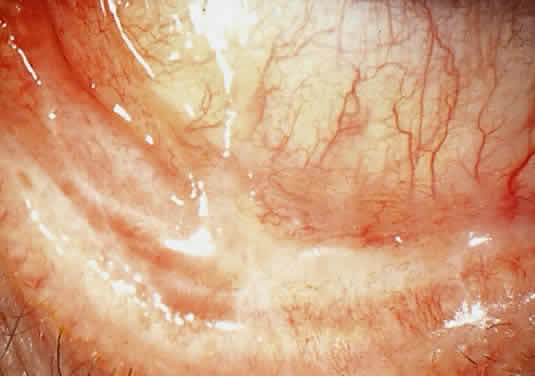

OCULAR FINDINGS. The outstanding clinical feature common to all three phenotypes is the corneal and conjunctival cystine crystal deposition (Figs. 3 and 4). Photophobia is often the only presenting visual symptom; this may be incapacitating and associated with blepharospasm.

Corneal deposits appear as a layer of homogeneously distributed, fusiform or needle-shaped, iridescent crystals situated in the stroma beneath the epithelium. In the infantile form, anterior crystal deposition begins early in life (between 6 and 15 months of age) and proceeds posteriorly as the patient ages; deposition advances more rapidly in the periphery. The anterior location of the crystals may be associated with recurrent erosions.33 The depth of the stromal deposition and the density of crystals is always greater peripherally than centrally. More and larger crystals occur in the superficial stroma. No visual impairment occurs at this early stage. By the age of 7 years, most patients have crystals, either within or on the endothelial surface34,35; markedly decreased corneal sensitivity is also present.36 The spherical contrast sensitivity function is significantly lower in infantile cystinosis than in age-matched controls.37

The conjunctiva has a ground-glass appearance. Polychromatic, polymorphic, rectangular, or rhomboidal crystals can be seen with the biomicroscope.

The uvea contains an abundance of polymorphous crystals. Clinically, these can be seen as glistening dots on the surface of the iris. Thickened iris stroma and posterior synechiae may occur; pupillary block glaucoma38 also has been reported. The entire uvea has polymorphic crystal deposition, most heavily in the choroid. The sclera also has crystal deposition.

The retinal abnormality consists of a generalized depigmentation that may assume a patchy pattern. At first the pigmentary disturbance tends to be peripheral, but it progresses with age. Macular abnormalities have been observed.39 Intracellular crystals also have been seen in the retinal pigment epithelial cells during electron microscopy.